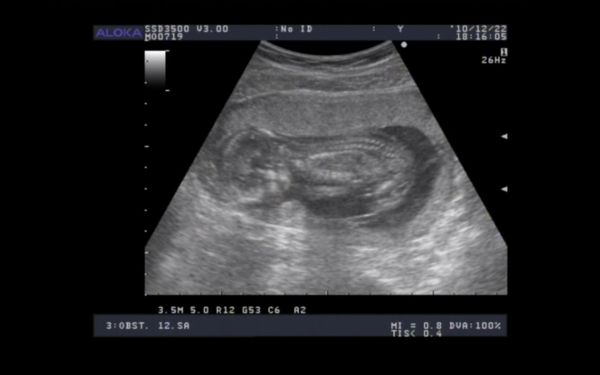

jah, és ahhoz, hogy ikrek még külön!

Zsó: Holnap Te gyere a jó hírekkel!!